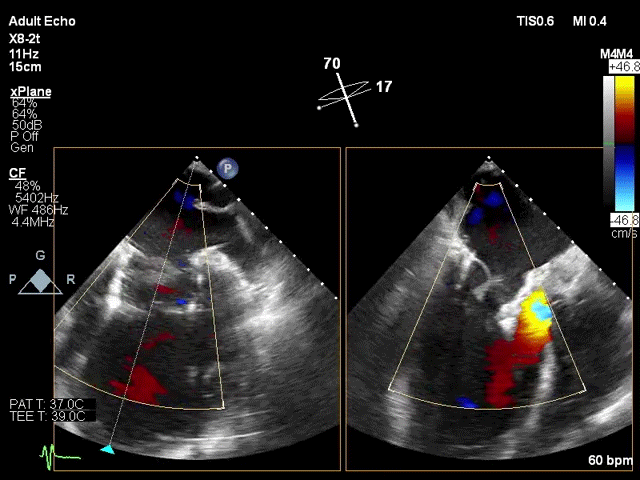

术前超声评估

该手术采用左侧第五肋间微创切口心尖入路,透视下经导丝置入输送系统,逐步释放瓣膜。透视及TEE确认瓣膜位置满意后撤出输送系统,二尖瓣瓣膜形态及工作状态良好,复查左心室造影,提示无瓣周漏,无左室流出道梗阻,左右冠状动脉显示良好,未受任何影响。

患者术后30天随访状态良好,随访显示左心室逆重构,左心室功能伴左心室结构显著改善,全面达成包含二尖瓣反流程度降低、心功能改善等有效性指标。人工二尖瓣工作正常,支架结构及形态稳定,锚固良好无位移,无瓣周漏。瓣叶开闭形态良好,血流动力学表现优异,平均跨瓣压差仅1mmHg。